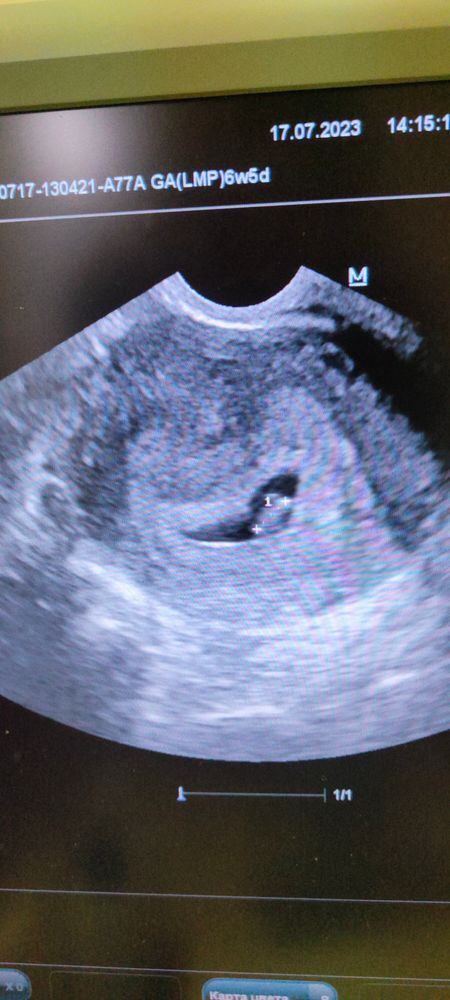

В УЗИ не разбираюсь, но у меня на 6 неделях услышали сердцебиение уже и выглядело УЗИ вот так

У вас ещё слишком маленький срок, он почти не просматривается. У меня абсолютно похожий был снимок на сроке 5 недель, но мне ничего подобного не говорили, кроме как прийти через пару недель. В итоге я сделала ещё снимок в 8-9 недель в другой клинике, на аппарате получше и там всё показало нормально, и сердцебиение в том числе.